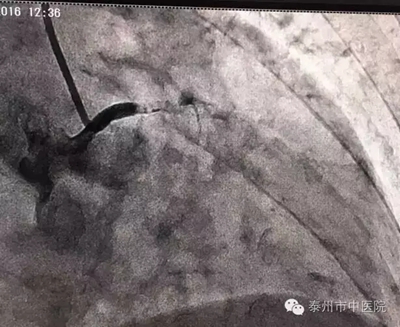

在與家屬溝通后,市中醫(yī)院心血管病科張永光主任等立即至導(dǎo)管室緊急冠脈造影。冠脈造影血管投影只見(jiàn)左主干近端,下方血管無(wú)顯影,明確為左主干閉塞。令現(xiàn)場(chǎng)所有醫(yī)護(hù)人員心驚不已!

左主干閉塞,是一例病情兇險(xiǎn)、病死率極高的病例!搶救刻不容緩?。堄拦庵魅蔚?,隨即開(kāi)展緊急救援,長(zhǎng)達(dá)一個(gè)小時(shí)的救治中,左主干再通,X線(xiàn)下可看見(jiàn)清晰的血管顯影。